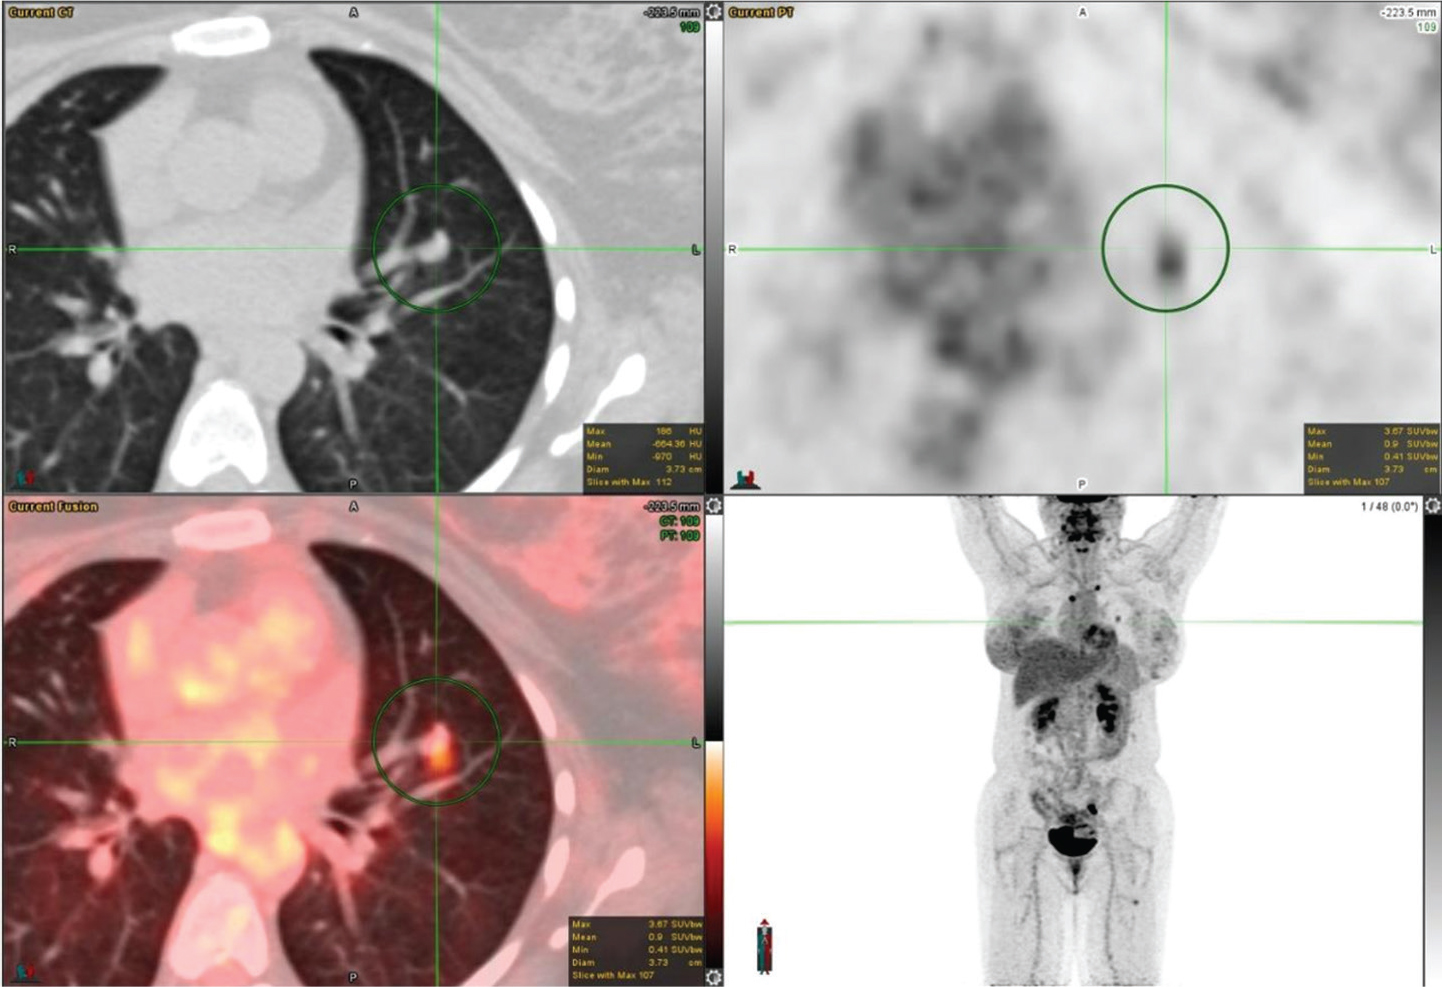

18F-FDG PET/CT has been widely studied for its use in the accurate characterization of SPNs because it localizes to the lesion proportionate to its metabolic activity. An example of an FDG avid SPN is shown in Figure 1. Solitary pulmonary nodules in PET/CT are analyzed qualitatively and quantitatively. Qualitatively, metabolic activity in the SPN is visually compared with the activity of the mediastinal blood pool; SNPs with metabolic activity greater than the mediastinal blood pool are likely malignant. For quantitative assessment, a standardized uptake value (SUV) can be used and SUV greater than 2.5 defines the SPNs as malignant with a relatively high degree of sensitivity and specificity (7). However, this 2.5 threshold is arbitrary as newer PET scanners generally provide higher uptake values than older machines. Additionally, the SUV is underestimated for small nodules due to the partial-volume effect, and for lower lung nodules near the diaphragm due to respiratory motion. Furthermore, in the past, when FDG PET imaging was a new modality, the 2.5 threshold was used, although it has been proven to be suboptimal subsequently, as low-grade malignancies can have low SUVs and active infectious/inflammatory etiologies can have high SUVs. However, SUV on 18F-FDG PET/CT correlates well with Ki-67 (a marker of cell proliferation) and the intensity of FDG uptake/SUV has a correlation with grade and aggressiveness of the lesion and consequently prognostic significance. Using these criteria, recent studies have shown a sensitivity of 92–96% and a specificity of 77–90% using 18F-FDG PET/CT for detecting malignancy (8). A multicenter study by Lowe et al. showed sensitivities of 100% and 80%, and specificities of 74% and 95%, for visual and SUV analyses of SPNs, respectively (9). A recent meta-analysis of studies using 18F-FDG PET/CT for the evaluation of SPNs showed a sensitivity of 96.8% and a specificity of 77.8% (7).

Fig 1

Figure 1. Right upper lung pulmonary nodule that was pathologically confirmed as invasive moderately differentiated adenocarcinoma. FDG PET/CT images include axial CT (top left panel), axial PET (top right panel), fused axial PET/CT (bottom left panel), and maximum intensity projection (MIP) PET image (bottom right panel). In the green circle, there is a right upper lobe pulmonary nodule on CT with intense FDG uptake on PET. There was additional mild to moderately FDG-avid lymph nodes (not on the included PET/CT images and faintly seen on the MIP image) that were suspicious for metastatic disease.